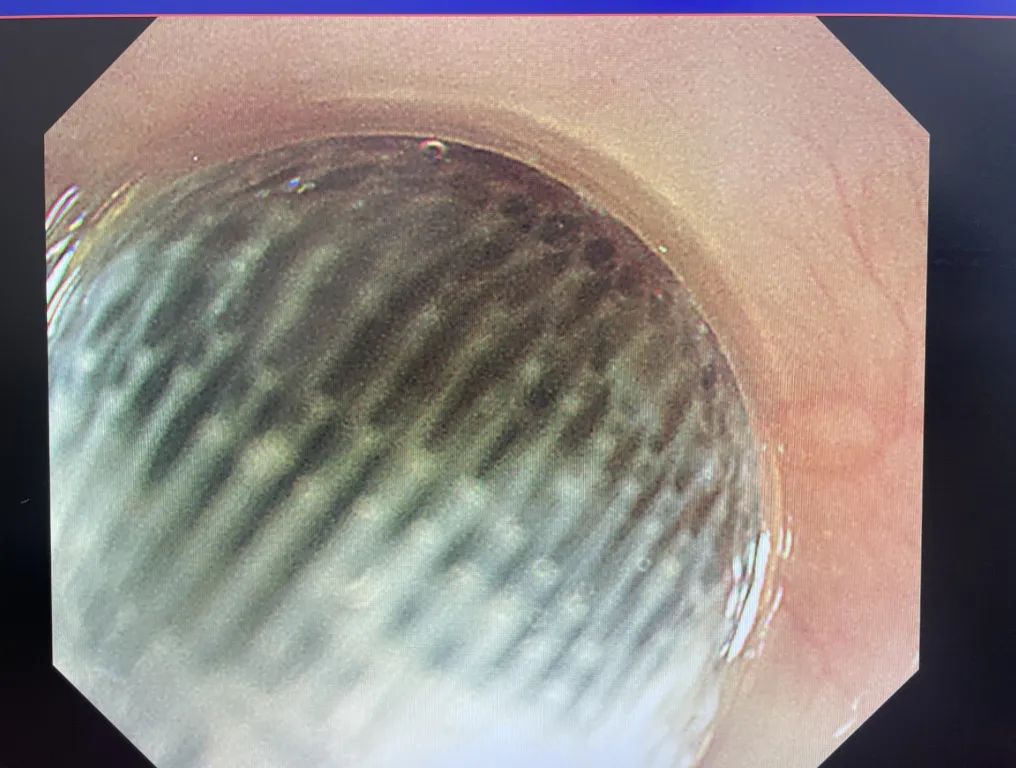

前来会诊的脾胃肝病科一区副主任医师刘伟锋评估发现,小明吞下的异物为椭圆形的金属磁铁玩具,重量比寻常异物重上许多,很容易导致胃肠道梗阻或穿孔。此外,在胃肠道蠕动反应下,异物将继续下滑,若进入曲折、窄小的小肠,发生梗阻的几率将进一步增大,取出难度也会直线上升,因此必须立即将其取出。

看看这个被取出的玩具,你家是不是也有?